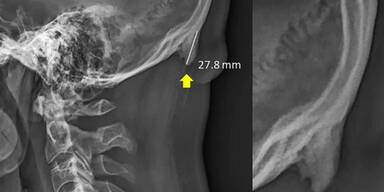

Australische Wissenschaftler haben eine Veränderung am Kopf entdeckt, die auf den Smartphone-Gebrauch zurückzuführen sei. Der sogenannte "Knochen-Stachel", "Handy-Knochen", "Handy-Horn" oder ganz schlicht "Zacken" ist eine Knochenwucherung am Hinterkopf, welche die Forscher beim Auswerten von Röntgenbildern vermehrt gerade bei jüngeren Menschen festgestellt haben. Jeder vierte unter 30-Jährige soll so ein Horn am Hinterkopf haben.

Ein aktueller Bericht der BBC führte dazu, dass die Studie nun neue Aufmerksamkeit bekam, meldete die "Washington Post". In australischen Medien seien die von den Forschern beschriebenen knöchernen Auswüchse, in der Fachsprache auch Exostose genannt, bereits als "Kopfhörner", "Telefonknochen" oder "Stachel" bezeichnet worden.

"Ganz egal, wie es genannt wird: Es sieht aus wie ein Vogelschnabel, ein Horn, ein Haken", zitiert die "Washington Post" den Studienleiter Shahar. Die Deformationen seien ein Zeichen für eine ernsthafte Fehlhaltung, die zu chronischen Kopfschmerzen und Schmerzen im oberen Rücken und Nacken führen können.